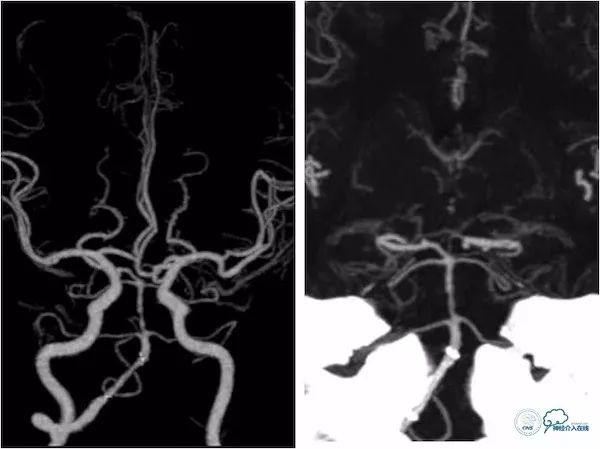

头颅MRA:右椎动脉V4段及基底动脉狭窄(图3)。

图3

头颈部CTA:左椎动脉闭塞,右椎动脉V4段狭窄,基底动脉局限性狭窄,双侧后交通动脉开放(图4)。

图4